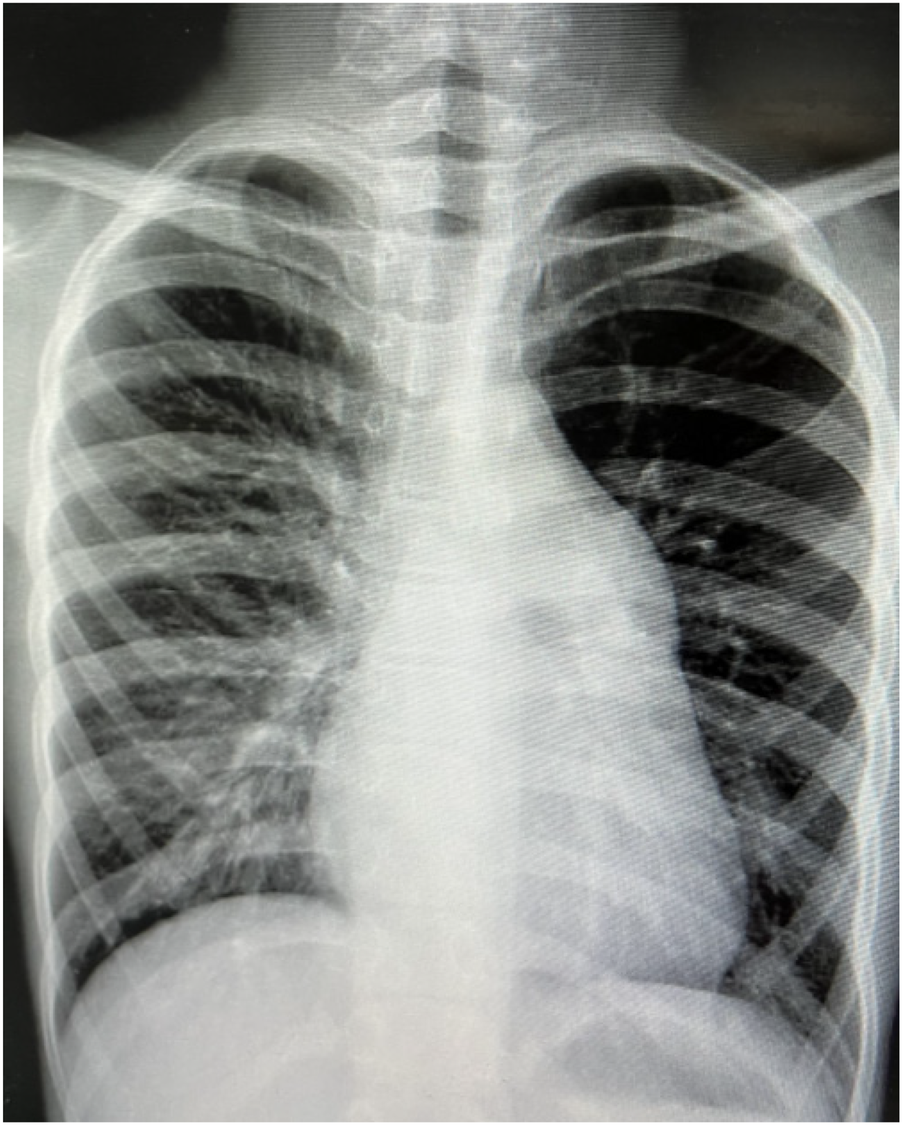

A 9-year-old female presented with a history of a cardiac murmur detected at age 1. Initial echocardiography (March 2016) revealed PDA, atrial septal defect (ASD), and PH. She reported symptoms including occasional dyspnea, reduced exercise tolerance compared to peers, post-exertional wheezing, squatting preference, cyanosis of the lips and lower extremities, and clubbing of fingers. Two prior attempts at PDA closure (May 2016 at another institution, and April 2018) were aborted due to persistently elevated pulmonary artery pressure (PAP) despite targeted therapy with endothelin receptor antagonists (ERA) and phosphodiesterase-5 (PDE5) inhibitors, initiated after the first failed attempt. Therapy evolved over time, including periods of triple therapy (ambrisentan, sildenafil, treprostinil) and dual therapy (ambrisentan + sildenafil), adjusted due to side effects and financial constraints. Upon admission to our center (January 2024) (Table 1, Figure 1, 2), physical examination revealed differential cyanosis (upper limb SpO2 90%–92%, lower limb SpO2 80%–82%), cyanotic lips, clubbing, an accentuated P2 heart sound, but no pathological murmurs. Echocardiography confirmed a large tubular PDA (10.3 mm, predominantly right-to-left shunt), secundum ASD (6.4 mm, bidirectional shunt), severe PH (estimated sPAP 97 mmHg), mild tricuspid regurgitation, and evience of right ventricular hypertrophy and dysfunction (TAPSE 11 mm, FAC 33%) (Table 2). Cardiac catheterization (March 2024) under general anesthesia confirmed precapillary PH (mPAP 57 mmHg, PCWP 9 mmHg, PVRi 11.24 WU-m2, descending aortic SpO2 77%, Qp/Qs 1.32). Following successful trial occlusion demonstrating a significant reduction in mPAP (to 45 mmHg) and normalization of descending aortic SpO2 (100%), a 20/22 mm Lifetech PDA occluder was deployed and real-time hemodynamic monitoring metrics (mPAP, PVR, SaO2). Postoperatively, triple therapy (sildenafil, ambrisentan, treprostinil) was continued. Follow-up at 3 months (June 2024) and 5 months (August 2024) post-closure showed marked clinical improvement: resolution of cyanosis (lower limb SpO2 91%–94%), improved exercise tolerance (6MWD) increased from 239 m pre-op to 333 m and then 390 m) (Table 3), and stable or slightly improved echocardiographic parameters (sPAP 100 mmHg at 3 m, 93 mmHg at 5 m; improved RV function TAPSE 19.7 mm/15.6 mm). The ASD remained patent.

Figure 1

Two color Doppler echocardiogram images show blood flow in a heart. The images use red and blue colors to indicate the direction and speed of blood flow within the heart chambers and valves.

Figure 1. Cardiac ultrasound of case 1 at guangdong provincial people's hospital (January 11, 2024).